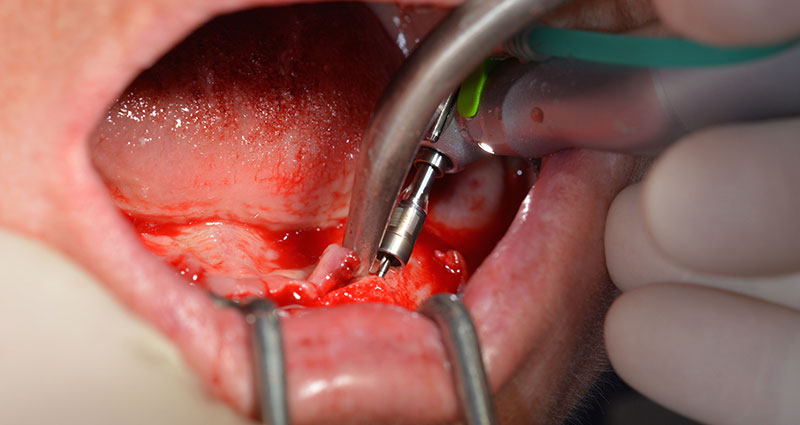

Le trou mentonnier doit d'abord être identifié comme une structure anatomique limitante, puis l'os cortical de la crête a été régularisé avec une pièce à main droite et une fraise sphérique de grande taille (Fig. 4).

C'est ici que l'Implantmed révèle ses premiers avantages. Le protocole chirurgical est prédéfini et les réglages sont enregistrés à des positions fixes. Les positions individuelles peuvent être sélectionnées en appuyant sur la position "P" de la commande au pied ou sur l'écran. La vitesse de 35,000 tr./min. à la position 1 dans ce cas apparaît aussi par de grands chiffres sur l'écran rétroéclairé (Fig 5 et 6).